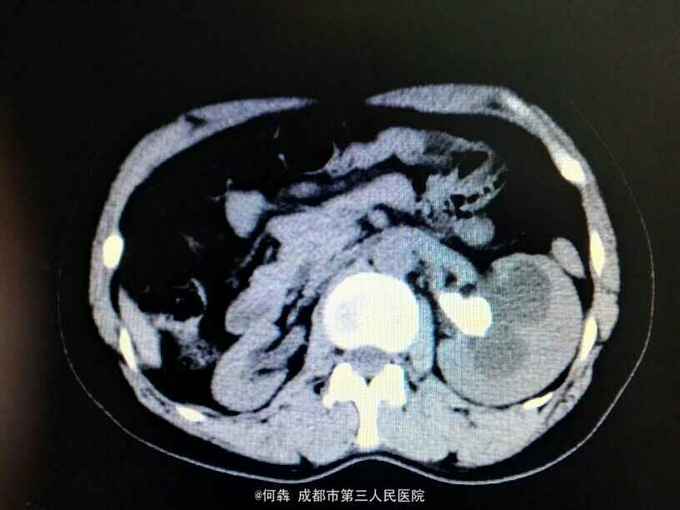

左肾区轻叩痛。尿常规:白细胞72个/ul。CT见图片。左侧GFR42.27,右侧GFR14.46。

左肾盂输尿管交界处结石 左肾重度积水,左肾结石,右肾萎缩,尿路感染。